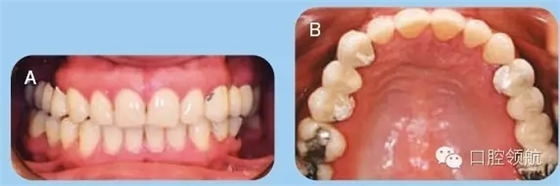

35歲白人女性患者,前來(lái)牙周科咨詢,要求修復(fù)兩側(cè)上頜象限的無(wú)牙頜區(qū)域。已存的固定橋修復(fù)失敗,患者要求行種植修復(fù)缺失牙。拆除患者已存的固定橋,重新預(yù)備基牙,并粘結(jié)臨時(shí)橋(圖1)。

圖1 (A)上頜以及下頜牙咬合關(guān)系的口內(nèi)照。(B)上頜牙弓的牙合面觀。

● 兩側(cè)上頜1/4象限的缺牙區(qū)牙槽嵴在頰舌向以及垂直向形態(tài)欠佳(Seibert III類(lèi))(圖1)。